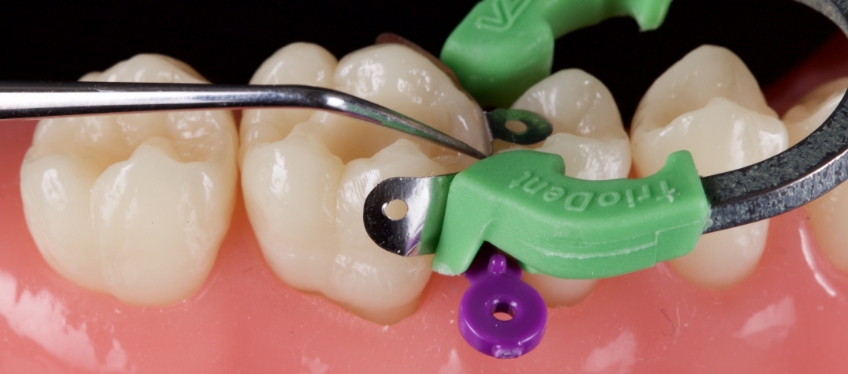

The occlusal portion of the Class II box is restored with conventional paste composite of the appropriate VITA shade. The thickness of this increment is maintained at 0.5-1.0 mm to reduce polymerization stress.

The composite is condensed with a microbrush. The marginal ridge is then refined with an explorer (American Eagle), which is held at 45 degrees to the long axis of the tooth; the explorer is moved from the center of the marginal ridge out toward the axial wall on the facial. Doing so refines the contour of the marginal ridge and pulls the resin towards the axial margin, reducing voids. This procedure is then repeated towards the lingual. Finally, a pulse activation strategy is employed to polymerize the resin.

The remaining Class 1 defect is then definitively restored using the occlusal compass approach.